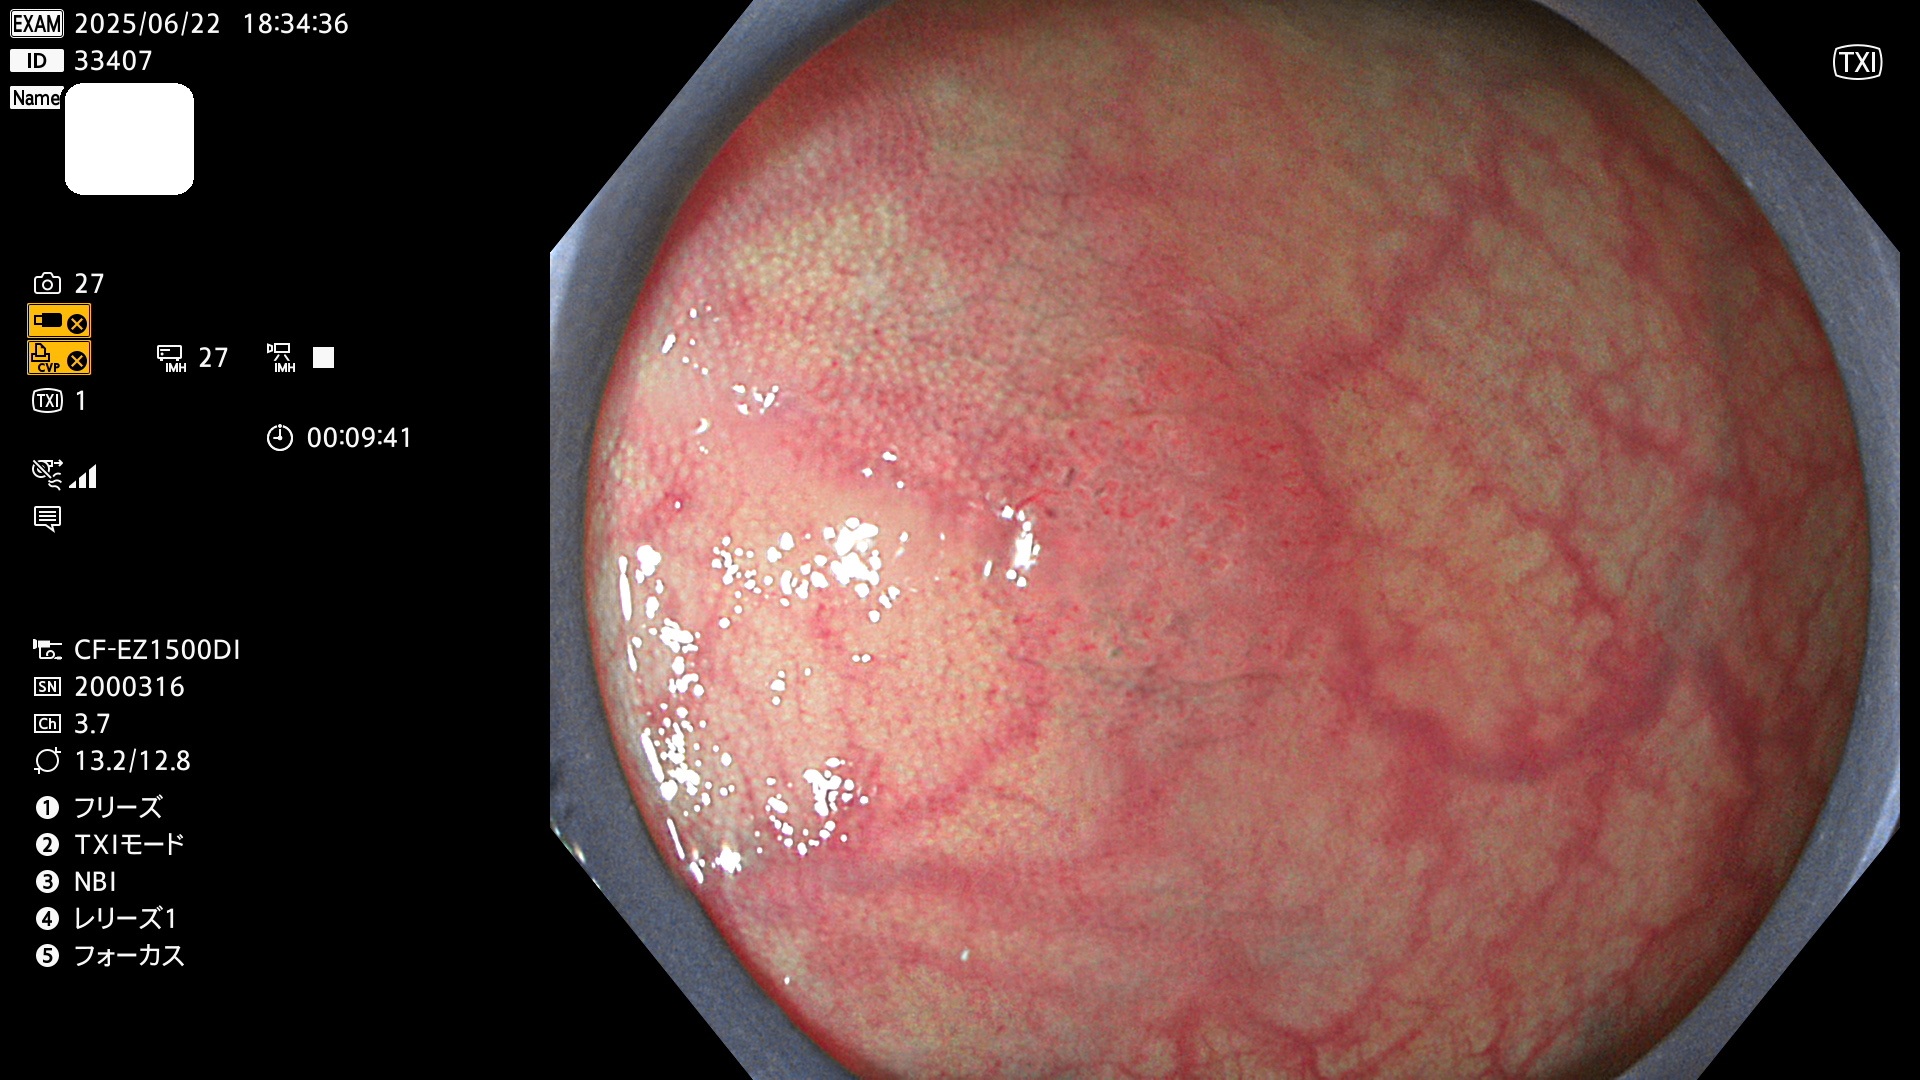

今週のUb、Uc型腺腫

完全に平坦な物をUb、陥凹している物をUcと呼びます。Ubは認識が困難で、Ucはびらん(炎症)と紛らわしいために見落とされやすく、「内視鏡後・大腸癌」の原因になります。

抽出の対象期間 2025年6月19日〜6月22日の4日間(48件の検査)10個 (10/48=20%)